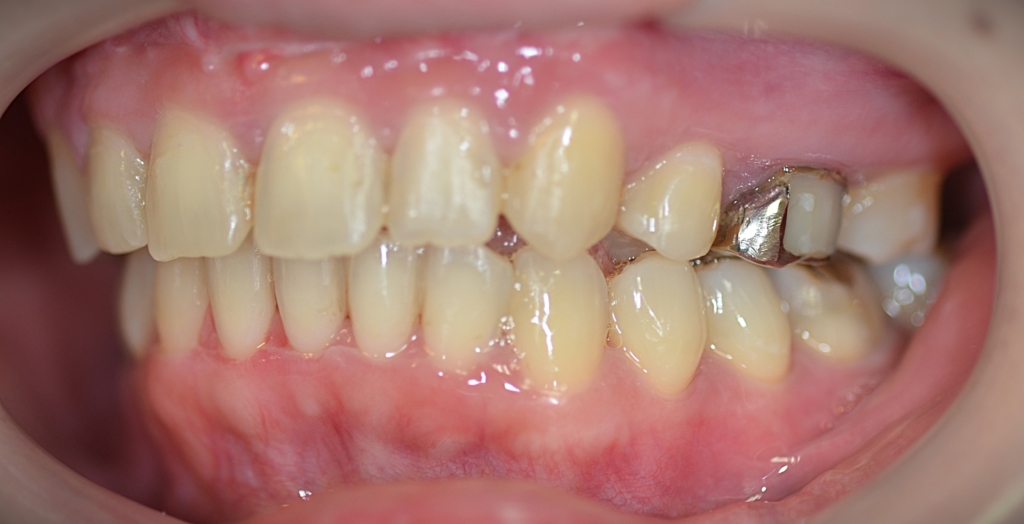

【Before】

【診断】

#1.上顎前突

#2.ガミースマイル(重度の過蓋咬合を伴う)

と診断しました。

補足:口腔前庭縮小術の既往あり(美容外科にて)